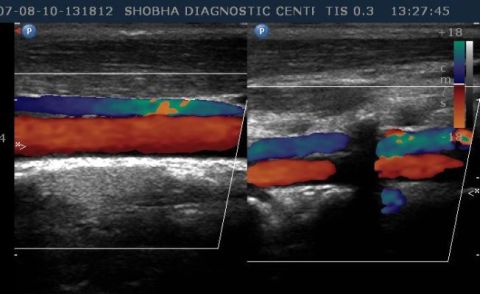

Color Doppler

Following Colour Doppler Examinations are performed at shobha diagnostic centre:

- Abdominal Doppler

- NECK VESSELS